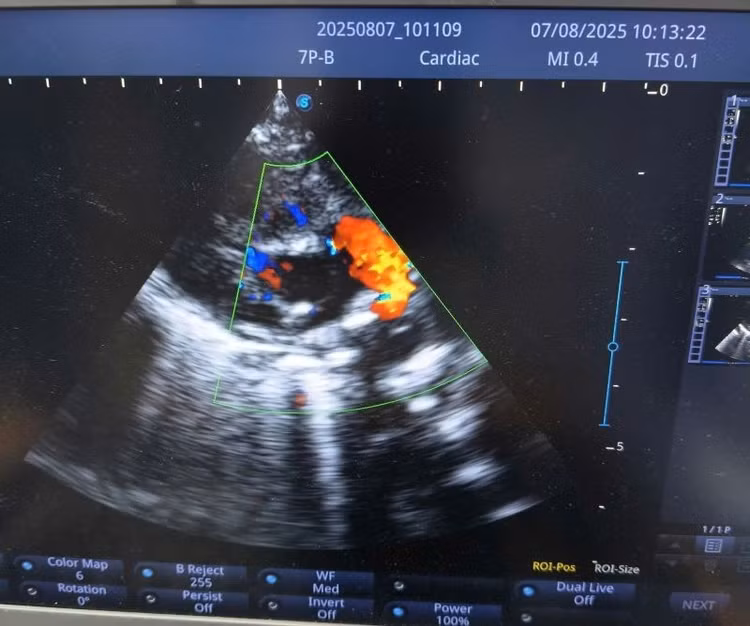

vien-chan-2.jpg

Dị tật tim bẩm sinh trên siêu âm - Ảnh BVCC